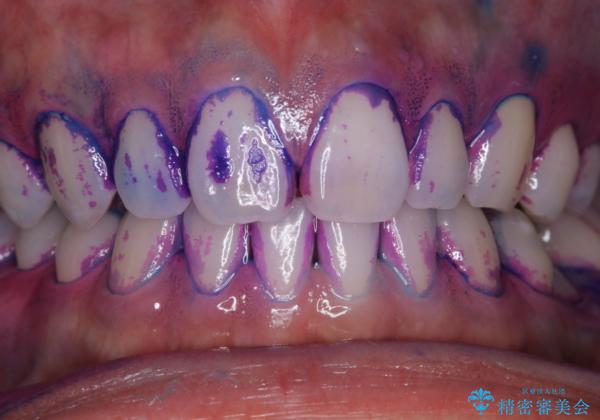

親知らずを抜いて1週間後にPMTC 歯のクリーニング

- 親知らずの抜歯後の約1週間後に抜糸(縫った部分の糸とり)で来院されました。その際、抜歯後は傷口が怖くて歯磨きが上手くできず、汚れや口臭が気になるためクリーニングも希望されました。

抜歯後は多少出血したり、違和感や痛みを感じたりすることがあります。そのため親知らずを抜いたり、外科的な処置をするといつも通りの歯磨きがしづらくなります。また、傷口の周りが心配で、歯ブラシをするのが怖くなるものです。抜歯後落ち着いたら、歯科医院にて専門の機械を使用しクリーニングをすることがおすすめです。抜歯前や後にPMTCを行うことで、お口の中の健康維持につながり、その後の感染・腫れ・口臭予防などになります。

親知らず抜歯後正常に治癒が進んでいれば1週間後から可能です。